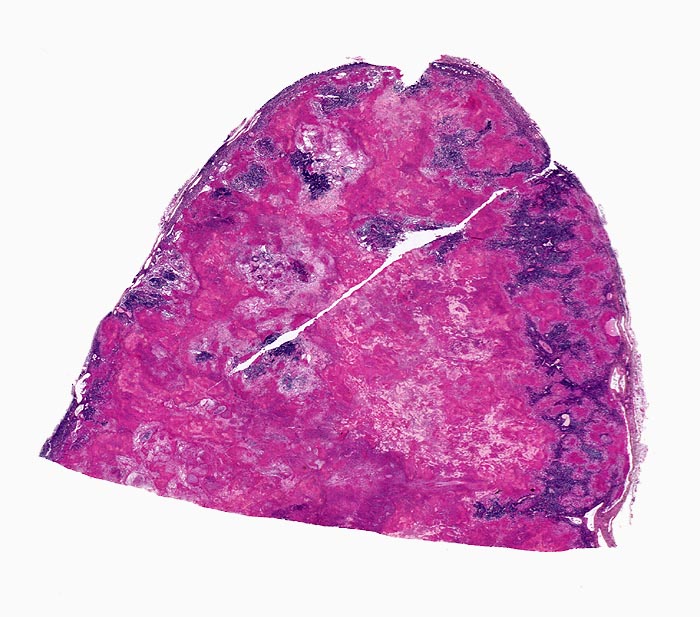

Basel 3BA HS/ Verkäsende Lymphknotentuberkulose

Verkäsende Lymphknotentuberkulose

• Lymphknoten mit ausgedehnten konfluierenden eosinophilen Nekrosezonen und nur wenig erhaltenem Lymphknotengewebe (blau).

• In den grösseren Nekrosearealen sind Kerntrümmer von neutrophilen Granulozyten erkennbar.

• Demarkierung der Nekroseareale durch schlanke Epitheloidzellen, Riesenzellen vom Langhanstyp mit hufeisenförmig angeordneten Kernen und Lymphozyten.

Virtuelles Präparat

Befund

Pathologischer Befund